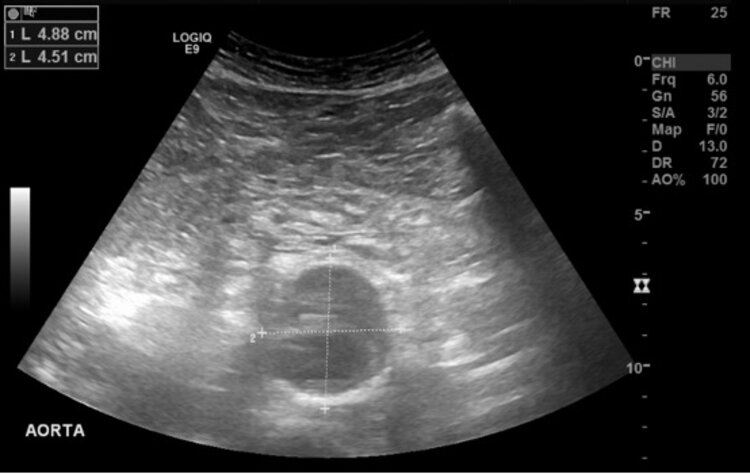

Die Diagnosestellung erfolgt in der Regel per Ultraschall, ist oftmals aber auch ein Zufallsbefund, so dass die Erstdiagnose auch in einem CT oder Kernspin erfolgen kann (Abbildung 1 a–c). Meistens jedoch wird zuerst mittels Ultraschall geschaut und ggf. im Anschluss eine CT- oder Kernspinuntersuchung durchgeführt um die genaue Grösse und Ausdehnung festzustellen.

Eine Ultraschalluntersuchung als Vorsorge zum Ausschluss eines Bauchaortenaneurysmas wird für Männer ab 65 Jahren empfohlen, im Falle einer familiären Häufung ist eine Ultraschalluntersuchung schon früher zu empfehlen.